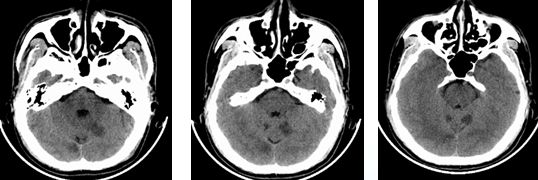

入院时颅脑CT(3.19)小脑梗塞

术后复查颅脑CT